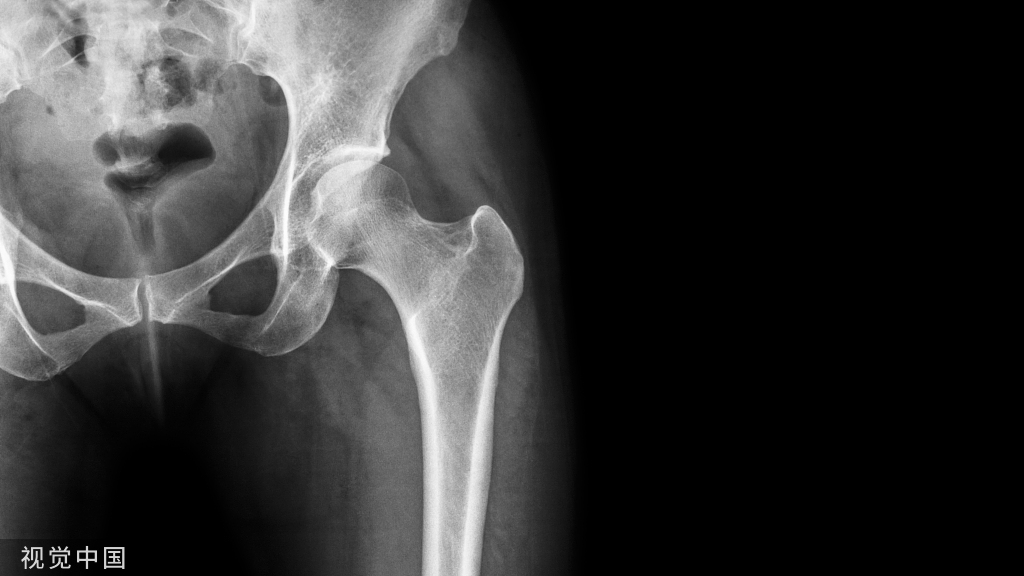

“四面体”型桡骨远端骨折概念:桡骨远端部分关节内骨折,骨折累及桡骨掌尺侧关节面及乙状切迹,横断位上呈三角形,骨折线延伸至桡骨干骺端。该骨折的特殊性体现在桡骨掌尺侧骨块的特殊性。一方面,掌尺侧骨块形成的月骨窝,作为抵抗腕骨向掌侧脱位的物理支撑,该结构的支撑作用消失导致腕关节掌侧脱位;第二,该骨块作为下尺桡关节桡骨关节面的组成部分,恢复其解剖位置是恢复下尺桡稳定性的前提。下图示病例1:典型“四面体”型桡骨远端骨折的影像表现。